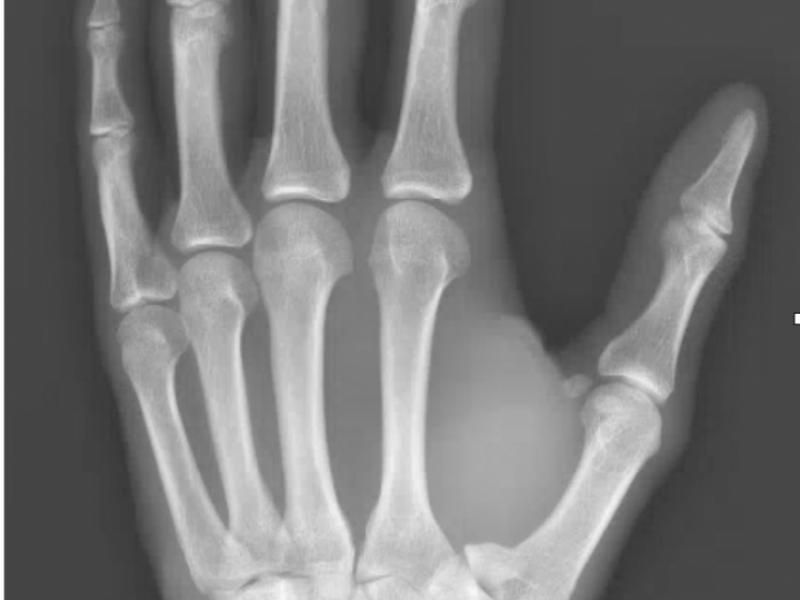

Back to Basics: First Metacarpal Fractures

Three types: Extra-articular, Intra-articular, Sesamoid Bone

A 31 yo male presents with left thumb pain after a dirt bike